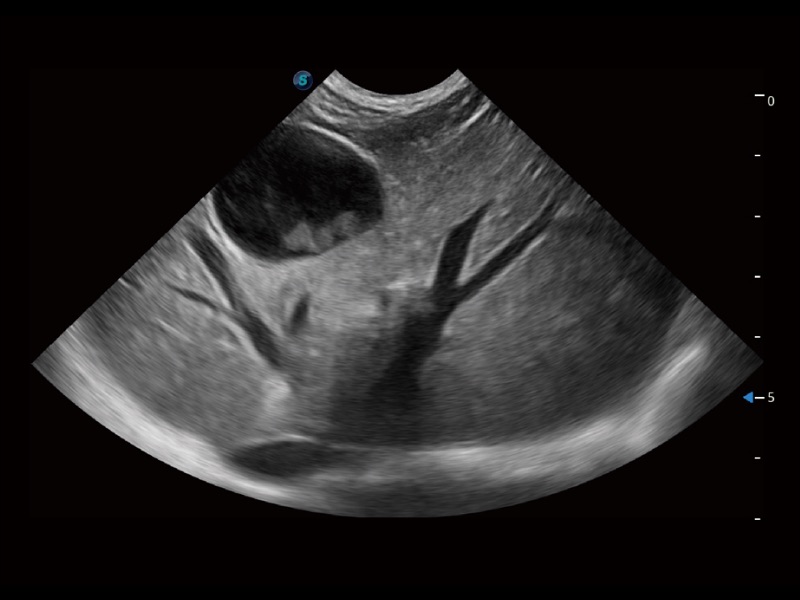

ProPet 70专为动物医生设计,对不同的动物体型和生理结构作出了针对性的优化。通过动物影像专用软件,可满足个性化的应用需求,帮助动物医生获得更精确的诊断数据。

为精细结构及组织边缘提供高清晰度的图像和更大的成像视野。帮助减轻医生的用眼疲劳,快速精准获得测量的数据。